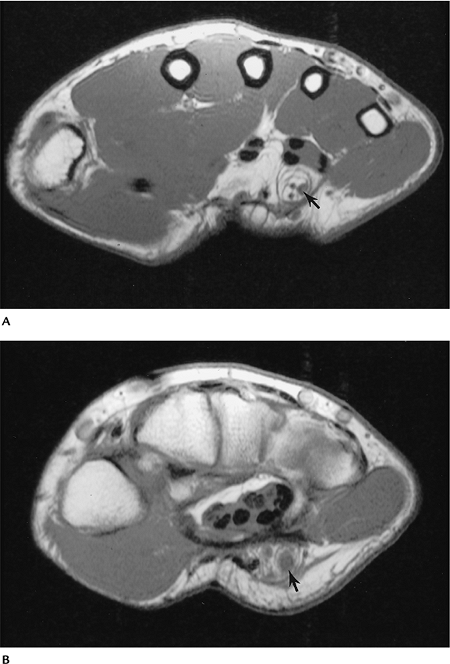

FIGURE 9-54 Fibrolipoma of the ulnar nerve. Axial T1-weighted images (A,B) demonstrate an enlarged low signal intensity nerve with associated fatty tissue (arrow).